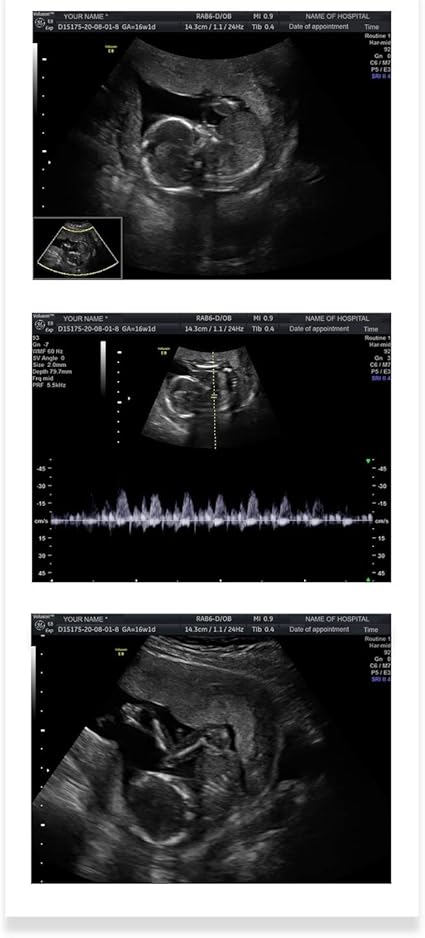

Ultrasonido De 4 Meses De Embarazo Youtube